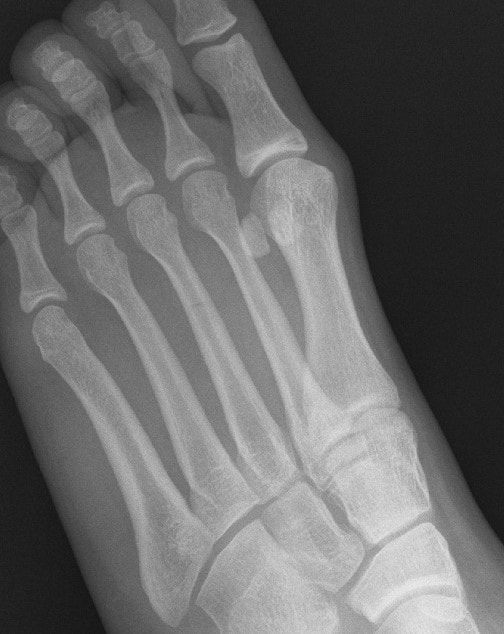

This is a stress fracture of the third metatarsal. To the right is a magnified view where a very subtle linear fracture lucency is clearly seen. The cortices remain intact and there is no evidence of callus.

Stress fractures occur commonly in people as a result of overuse from a sudden increased activity level or people who do a lot of activity with their legs (runners, dancers, jumpers, military marching). A second category of affected patient's includes those with weakened bones such as from osteoporosis or other metabolic or neuropathic conditions such as diabetes. Changes in footwear, training surface, or poor technique can also factor into developing a stress fracture. These are most common in the second and third metatarsals which absorb greater amounts of stress during foot push off.